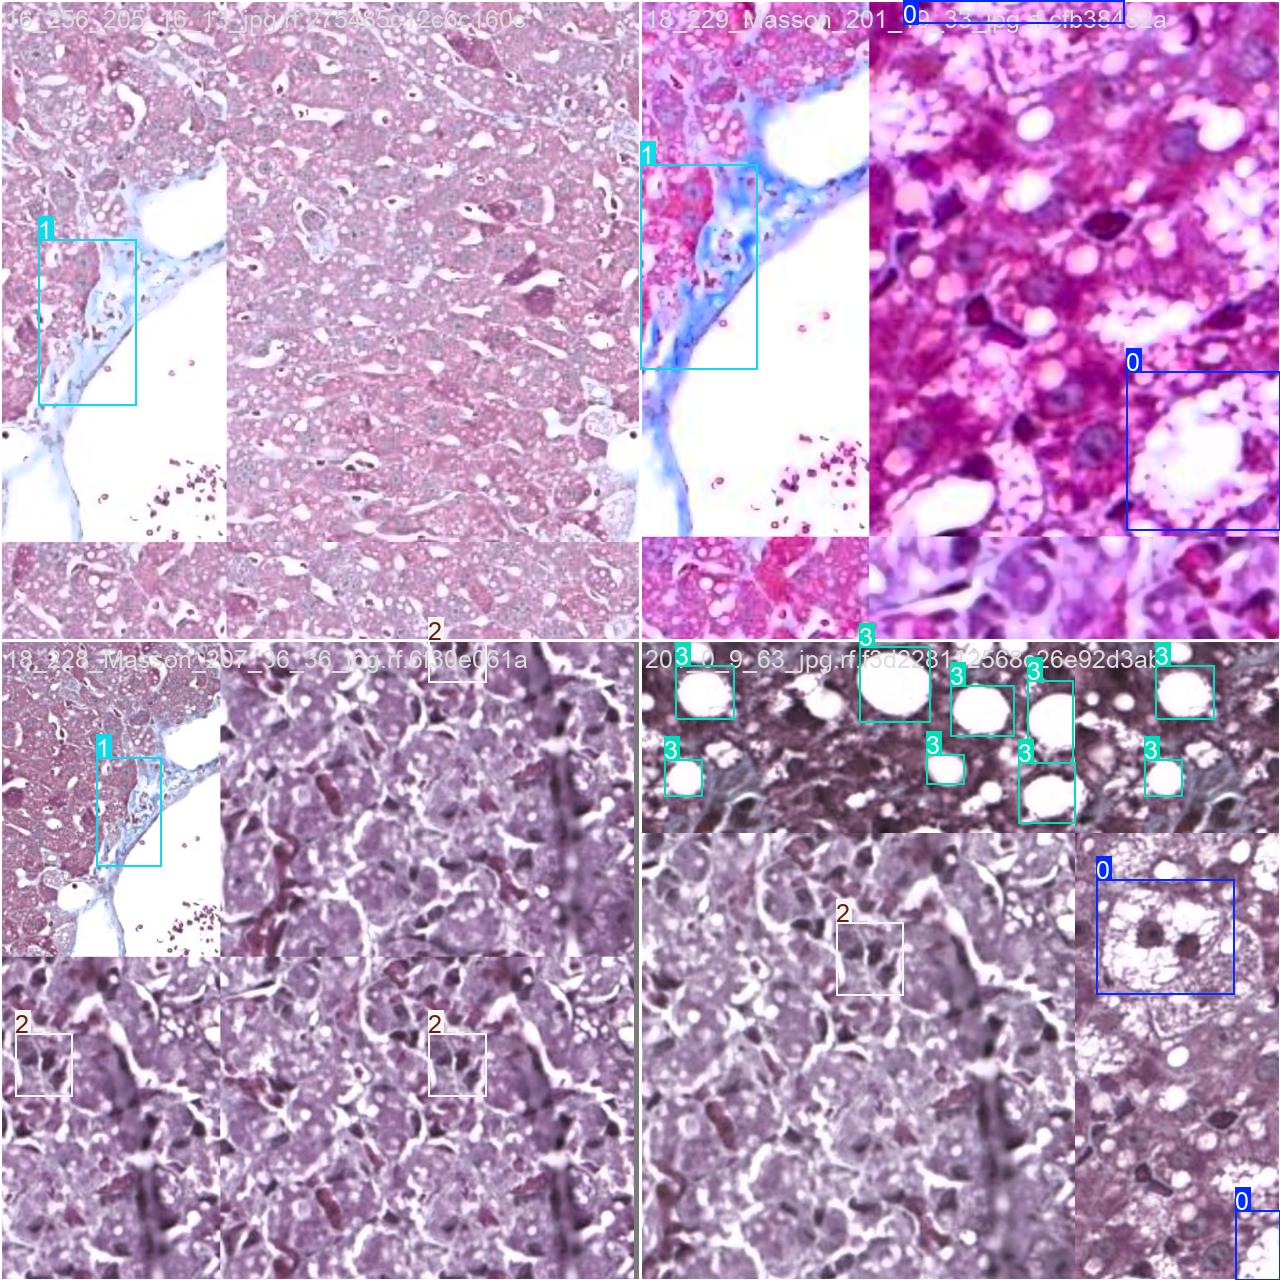

2.数据集准备与训练

本研究使用了包含各种肝病相关图像的数据集,并通过Labelimg标注工具对每张图像中的目标边框(Bounding Box)及其类别进行标注。然后主要基于YOLOv8n这种模型进行模型的训练,训练完成后对模型在验证集上的表现进行全面的性能评估及对比分析。模型训练和评估流程基本一致,包括:数据集准备、模型训练、模型评估。本次标注的目标类别为细胞膨胀、纤维化、炎症、脂肪肝,数据集中共计包含3976张图像,其中训练集占2782张,验证集占794张,测试集占400张。部分图像如下图所示:

部分标注如下图所示: